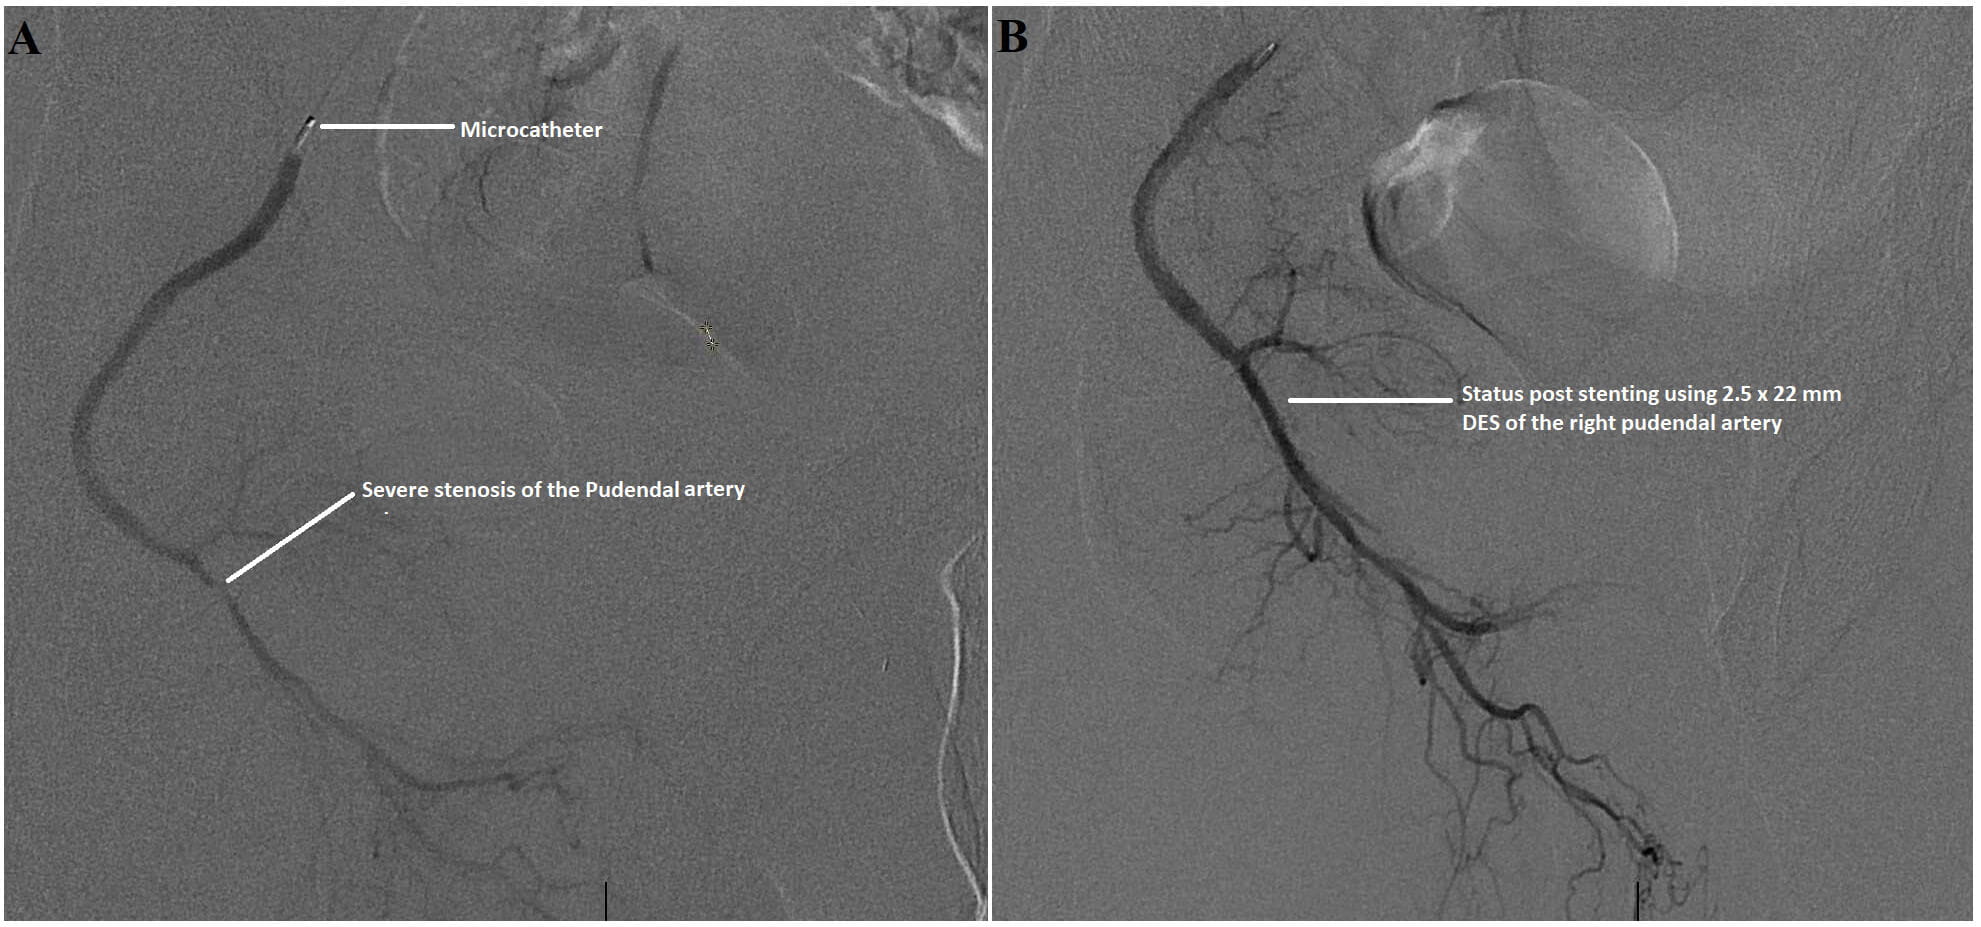

Severe atherosclerotic stenosis of the right pudendal arteryCaption: Severe atherosclerotic stenosis of the right pudendal artery (Panel A), in a middle-aged man with erectile dysfunction, was treated successfully and percutaneously using a drug eluting stent (Panel B).